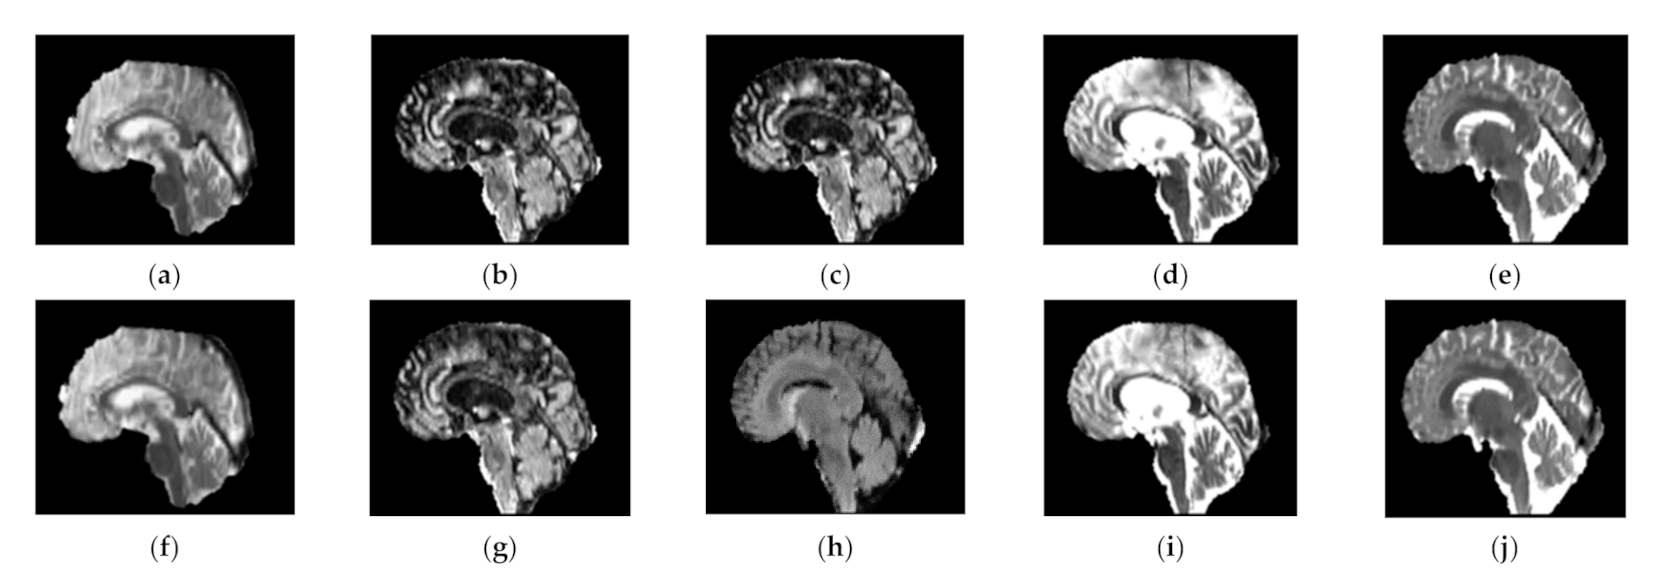

Using this approach, the high frequency components along the direction are enhanced and due to the normalization Gx + Gy = 1, where the artifact free images, i.e., Jx = Jy remain unchanged as given in Equation (6), which ensures that the minimal smoothing is introduced [31]. The results produced by Gibbs ringing artifact removal [31] are shown in Figure 2 below.

Figure 2.

BraTS MR images, before (top row) and after (bottom row) Gibbs ringing artifact removal. Each MR image in top row (a–e) has the corresponding Gibbs ringing artifact-removed MR image (f–j) in the bottom row. All the images shown here are T1ce-saggital (for fair comparison). However, other sequences, i.e., FLAIR, T1 and T2 can also be addressed for ringing artifacts.

The top row of Figure 2 shows some sample images from the BraTS 2018 (extension of BraTS 2013 and BraTS 2015) dataset, which exhibits Gibbs ringing artifact. Each image in the top row has a corresponding image in the bottom row, where top row images show that these images are affected by Gibbs ringing artifact and the corresponding bottom row images are Gibbs ringing artifact removed images of the top row. We noticed that a good number of images from the BraTS dataset have the ringing artifact but for the sake of presentation, we added some of the sample images.